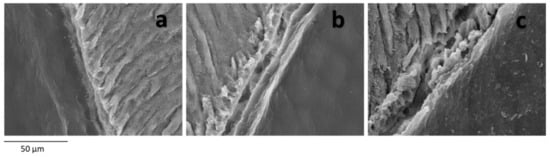

In the DEJ at the superficial level, alterations were found in 64% of the primary teeth. In 28% of the sample, a partial fracture of the DEJ was observed, with alternation between regions with normal junction and altered areas; in 28%, a complete solution of continuity of the DEJ was observed with a clean separation between enamel and dentin (Figure 2b), without adherent remains of enamel; in 8% there is a total tissue separation including remains of enamel prisms (Figure 2c). The most frequent finding in OI-I was to find a partial separation of the DEJ, while in teeth with OI-IV it was to find a clean separation between enamel and dentin, and in teeth with OI-III it ranged between mild alteration and clean continuity solution. Clean rupture of the DEJ with both tissues separated was more frequent than the presence of a disruption with the remains of adhered enamel prisms in the three types of OI analysed. Despite the differences described, statistically no relationship was found between the alterations of the DEJ and the type of OI (p value = 0.956), although there were significant differences with respect to the control group (p value = 0.004) (Figure 2a).

Figure 2.

DEJ. SEM photomicrographs with original magnification of 1000×. Image of a normal DEJ, with union between enamel and dentin (a), clean continuity solution between enamel and dentin with a clean gap between enamel and dentin without tissue adhesions (b) and fracture of enamel and dentin with remains of enamel prisms adhered to dentin (c).

The DEJ was analysed at the cervical level. In the same way as at the superficial level, the clean separation between enamel and dentin was the most frequent (44%), being more common in OI-IV and OI-III than in OI-I, and the alteration of the DEJ due to total fracture but adhered tissue remnants only occurred in one tooth of a patient with OI-I and another with OI-III. The data analysis showed that these differences in the involvement of the DEJ at the cervical level and the type of OI are not significant (p 0.351), although the differences with respect to the control group are significant (p < 0.001).

There is controversy about the involvement of the DEJ, because in some studies it is stated that the DEJ has a normal structure and function [10,16,17,29], while some [17,20] state that it is altered. Lindau and collaborators [20] describe the alternation of pathological and normal regions. They also established that the normal, scalloped appearance is more frequent in the cervical third of the DEJ. In our sample, in 28% of primary teeth a complete separation of the DEJ was observed, with the most common finding being a fracture of the union in which the enamel and dentin were separated and less common a fracture of the joint in which there are traces of enamel adhered to the dentin, and therefore, we assume that it is due to faults in the enamel and not only in the DEJ. In 28%, the alterations found were very heterogeneous, with partial fractures of the DEJ being observed and altered and non-altered areas coexisting. The failure of enamel and dentin to cross-link can lead to poorer mechanical retention between both tissues and therefore to functional failure of the DEJ. This retentive failure of the enamel on the dentin would advantage the detachment of the dental enamel.